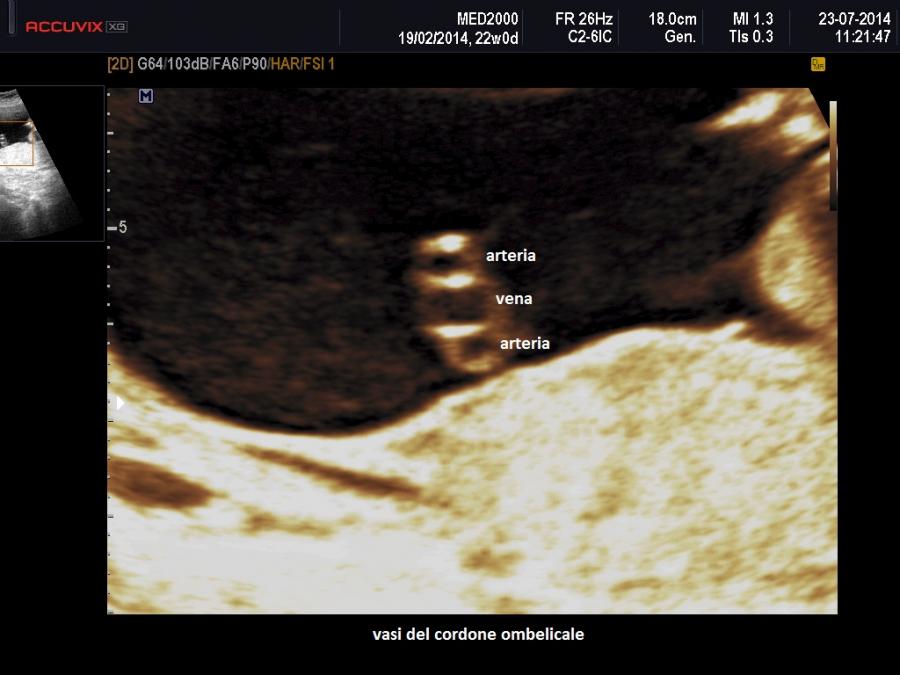

Il cordone ombelicale presenta normalmente tre vasi: una vena e due arterie, destra e sinistra. L'Arteria ombelicale singola (SUA) è una anomalia del sistema vascolare del feto in cui manca una delle due arterie.

Note di embriologia: negli stadi precoci della vita intrauterina i vasi del cordone sono 4, due vene e due arterie; intorno alla sesta settimana di gestazione la vena ombelicale di destra si chiude rimanendo solo la sinistra. Il cordone ombelicale definitivo è quindi formato dalle due arterie ombelicali, destra e sinistra, e dalla vena ombelicale di sinistra.

Il segno ecografico caratteristico è la presenza di due soli vasi nel cordone ombelicale. Al color-Doppler si osserva un solo vaso lateralmente alla vescica. In scansione trasversa si osserva un cordone con due soli vasi. Spesso l'unica arteria presente nel cordone va incontro ad una dilatazione compensatoria e mostra un calibro superiore ai 4 mm.; anche gli indici di resistenza risultano al di sotto della media per l'epoca gestazionale.